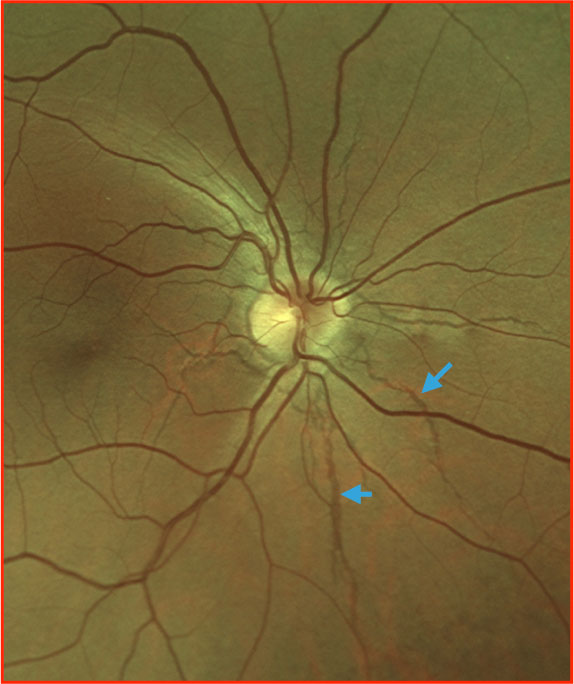

Angioid streaks (blue arrows) can be noted as reddish-brown lines emanating from the optic nerve head. They represent breaks in Bruch’s membrane and are commonly associated with systemic diseases (pseudoxanthoma elasticum among others). On autofluorescence these streaks can be noted as hypoautofluourescent areas. Furthermore, autofluorescence imaging often aids with visualization in more subtle cases.